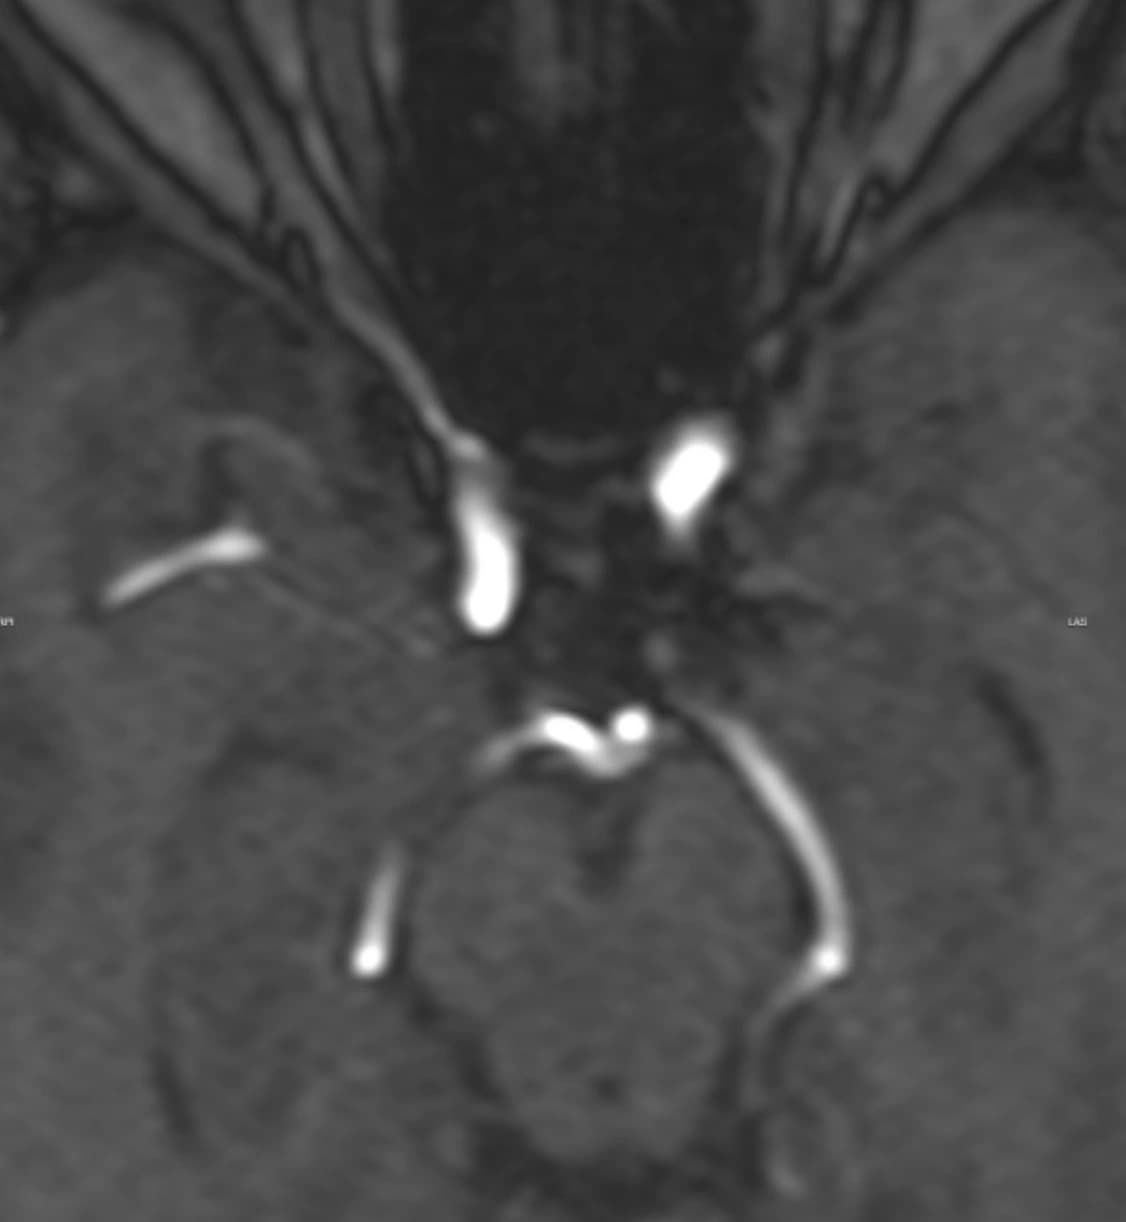

Two years later, Lynn returned to TrueScan for her follow-up Full-Body MRI. Her 2026 report confirmed that she had undergone successful endovascular coiling of the aneurysm, and today's MRA showed no discernible residual or blood flow within the aneurysm sac.

Her radiologist compared the pre-coiling and post-coiling images side by side in the report, confirming stability and recommending continued surveillance per her neurosurgeon's protocol.